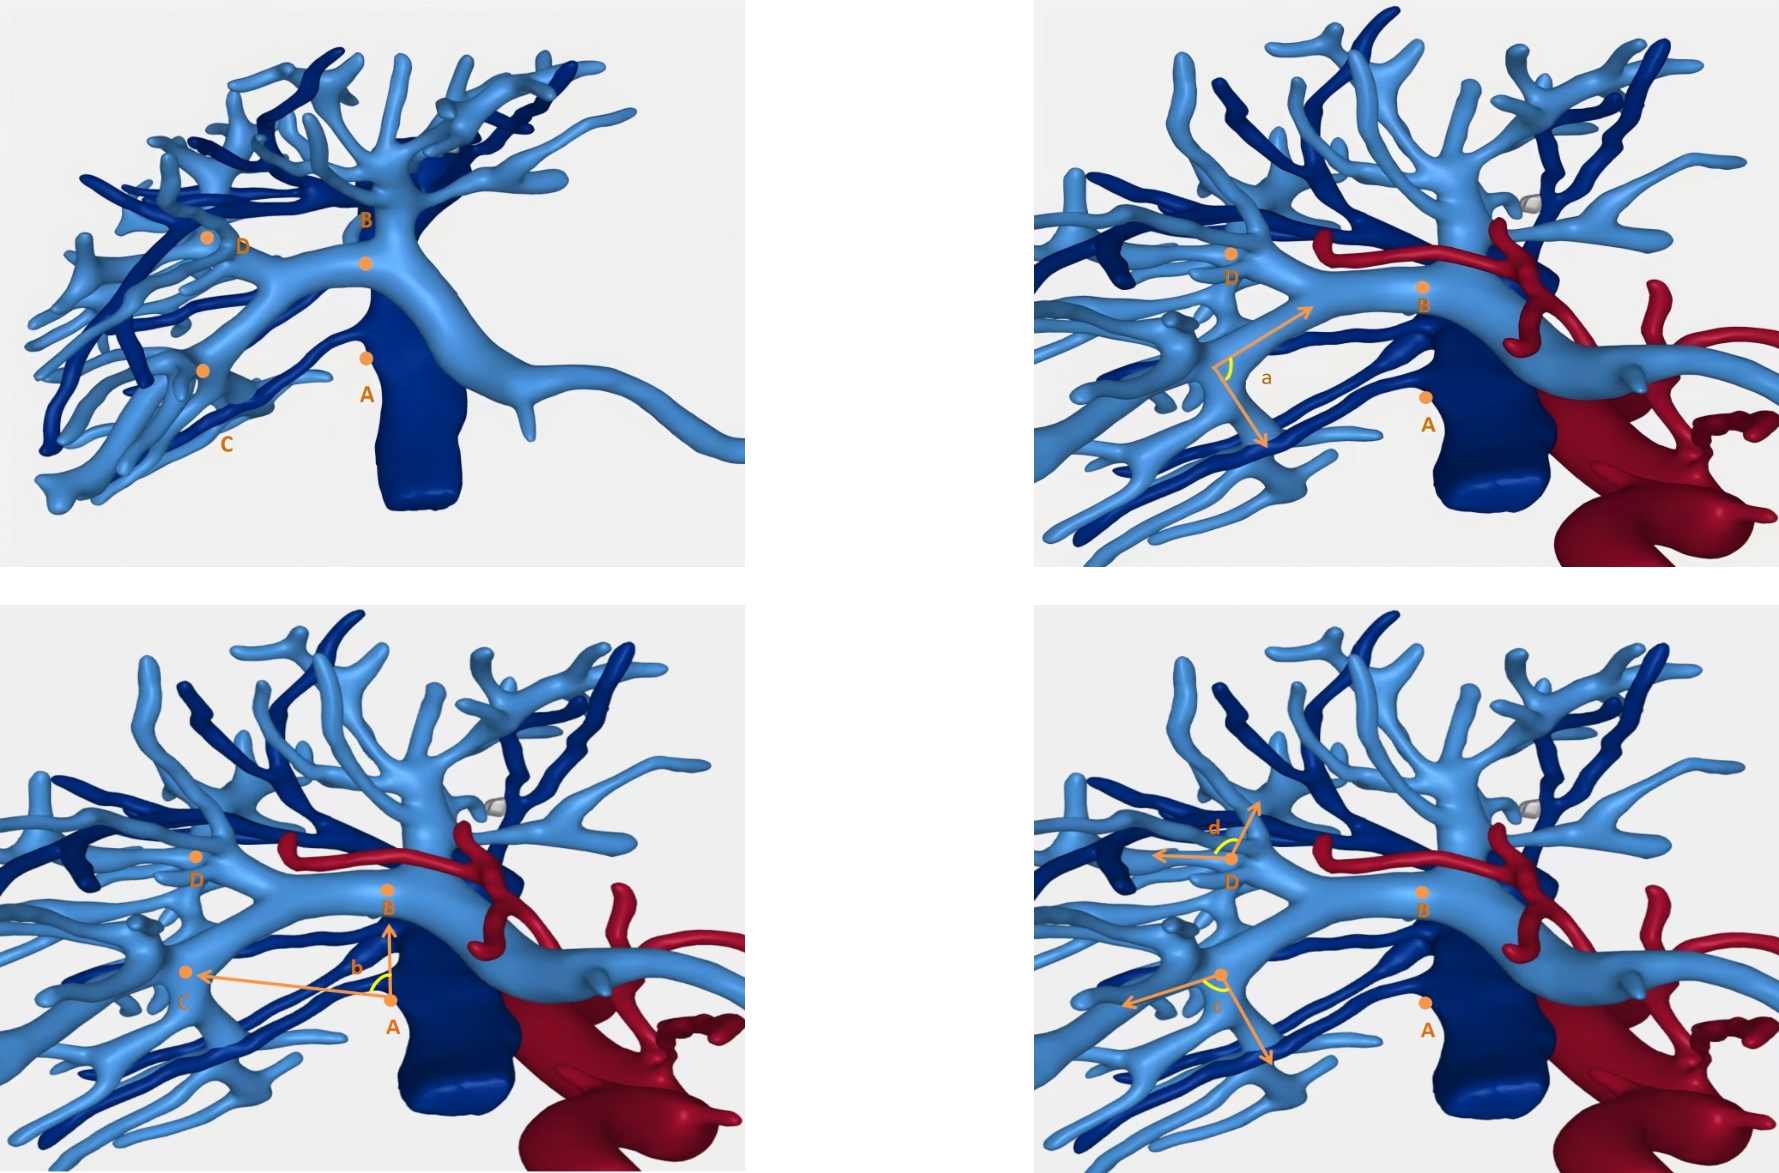

Background and Aims Precise identification and control of segmental Glissonian pedicles are fundamental to laparoscopic anatomical liver segmentectomy. However, marked anatomical variations, particularly in the right hemiliver, pose significant technical challenges. Based on the anatomical concept of the hepatic Laennec's membrane, this study aimed to systematically investigate the applied anatomy of Glissonian pedicles at the hepatic hilum and to establish practical anatomical landmarks for laparoscopic anatomical liver resection.Methods Six intact adult human liver specimens without macroscopic lesions were dissected under the guidance of the Laennec's membrane concept. The segmental Glissonian pedicles at the first porta hepatis were meticulously isolated, and the intervening liver parenchyma was removed. The origin, branching patterns, and spatial courses of Glissonian pedicles in each hepatic segment were analyzed. For the right hemiliver, a localization system consisting of four anatomical landmarks, two reference lines, and four characteristic angles was proposed and quantitatively evaluated using specimen measurements combined with CT imaging and three-dimensional liver reconstruction.Results The intrahepatic Glissonian system demonstrated both consistent patterns and pronounced individual variations. In the left hemiliver, the Glissonian pedicles of segments Ⅱ and Ⅲ usually arose independently, while segment Ⅳ commonly presented a bifurcated pattern with occasional multiple branches. In contrast, the right hemiliver showed substantial variability: segment V pedicles were frequently multibranched and often received contributions from segment Ⅵ; segment Ⅵ served as a pivotal pedicle with multiple branches contributing to segments V and Ⅶ; segment Ⅶ most commonly originated from the root of the right posterior pedicle, although in some cases it was formed by distal extensions of segment Ⅵ; segment Ⅷ pedicles were relatively constant in morphology, typically consisting of one or two branches. The proposed anatomical landmarks and quantitative parameters enabled clearer spatial localization of segmental Glissonian pedicles in the right liver.Conclusion Systematic dissection of segmental Glissonian pedicles guided by the Laennec's membrane concept, together with a quantitative anatomical landmark system, enhances the understanding of their spatial anatomy and variations. This approach provides practical and reliable anatomical guidance for precise and safe laparoscopic anatomical liver segmentectomy.

SHEN Zhengchao, CHEN Zhiyuan, XI Shihang, PAN Xuan, QIAN Daohai, MUHAMMAD Danish Irshad, WANG Xiaoming

2026,35(1):88-96, DOI: 10.7659/j.issn.1005-6947.250468

Background and Aims Laparoscopic resection of centrally located hepatic tumors remains technically demanding due to the complex anatomical relationships with major vascular structures. Conventional intraoperative ultrasound or indocyanine green fluorescence imaging (ICG-FI) alone has limitations, particularly in visualizing deep anatomical structures. This study aimed to evaluate the clinical value of augmented reality (AR) navigation combined with ICG-FI in laparoscopic resection of central hepatic tumors.Methods A retrospective analysis was conducted on 38 consecutive patients who underwent laparoscopic resection of central hepatic tumors guided by AR navigation combined with ICG-FI between May 2022 and March 2025. Intraoperative navigation performance, surgical parameters, and perioperative outcomes were assessed.Results All 38 procedures were completed laparoscopically without conversion. The intraoperative tumor fluorescence detection rate was 100%. The mean operative time was (324.9 ± 132.4) min, and the median intraoperative blood loss was 400 (50-1 200) mL. The mean registration error was (6.3±0.6) mm. The median number of predicted and verified vessels was 6 (4-8) and 7 (5-10), respectively. R0 resection was achieved in all patients, with a mean surgical margin of (1.5±0.5) cm. The postoperative complication rate was 13.2%, with no severe complications such as intra-abdominal hemorrhage, gas embolism, or liver failure. The median postoperative hospital stay was 9 (4-20) days. During a median follow-up of 20 months, no tumor recurrence was observed.Conclusion The combined use of AR navigation and ICG-FI enables intraoperative prediction and verification of critical vascular structures and facilitates precise control of the transection plane in laparoscopic resection of central hepatic tumors. This technique improves surgical precision and safety and shows promising clinical potential.